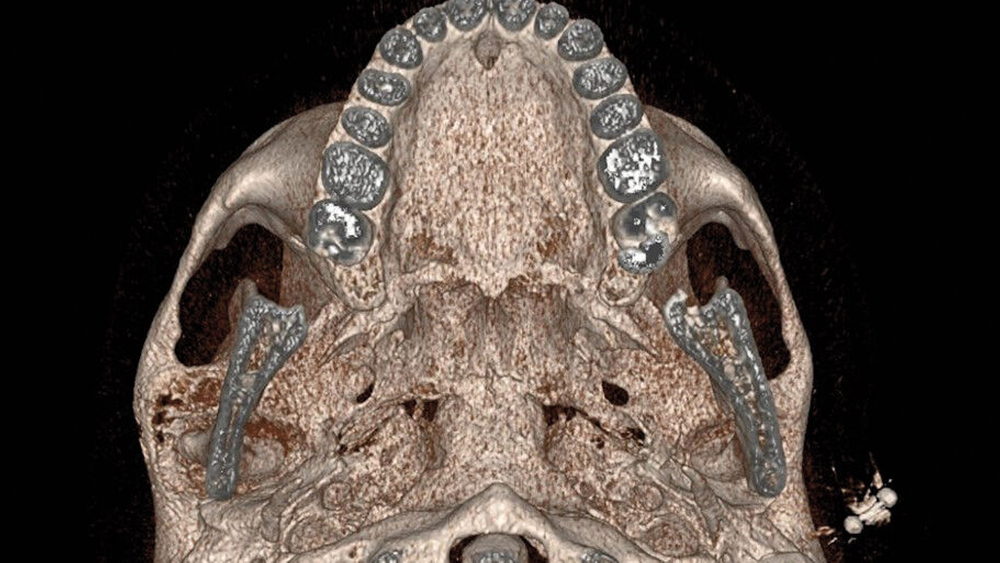

Im MRT und CT zeigte sich eine expansiv wachsende, überwiegend mattglasartige Knochenveränderung mit osteolytischen Anteilen und Unterbrechungen der Knochenstruktur, insbesondere in den unteren Partien nahe dem Kiefergelenk. Die Läsion war mit vermehrter intraossärer Kontrastmittelanreicherung assoziiert, was für eine fibröse Dysplasie spricht. Das Kieferköpfchen war abgeflacht, und es lag eine geringe Flüssigkeitseinlagerung im Kiefergelenk vor. In der Bildgebung fanden sich keine Hinweise auf eine Beeinträchtigung der umliegenden Foramina oder angrenzender Knochenstrukturen wie des Keilbeins (Abbildung 1).

Die Diagnose der CFD basiert in der Regel auf bildgebenden Verfahren, insbesondere der Computertomografie. Typisch ist dabei das sogenannte milchglasartige Erscheinungsbild des geflechtartigen Knochens, wie im vorgestellten Fall. Allerdings können die Läsionen sehr unterschiedlich erscheinen und auch sklerotische, zystische oder gemischte Strukturen aufweisen. Zu den differenzialdiagnostischen Überlegungen zählen unter anderem Meningeome, die Paget-Krankheit, niedriggradige Osteosarkome sowie verschiedene benigne fibroossäre Läsionen. Bei CFD-Läsionen mit maligner Entartung werden in der Bildgebung eine Destruktion der Kortikalis und eine Zunahme der Ausdehnung ins Weichgewebe beschrieben [Sun et al., 2014].